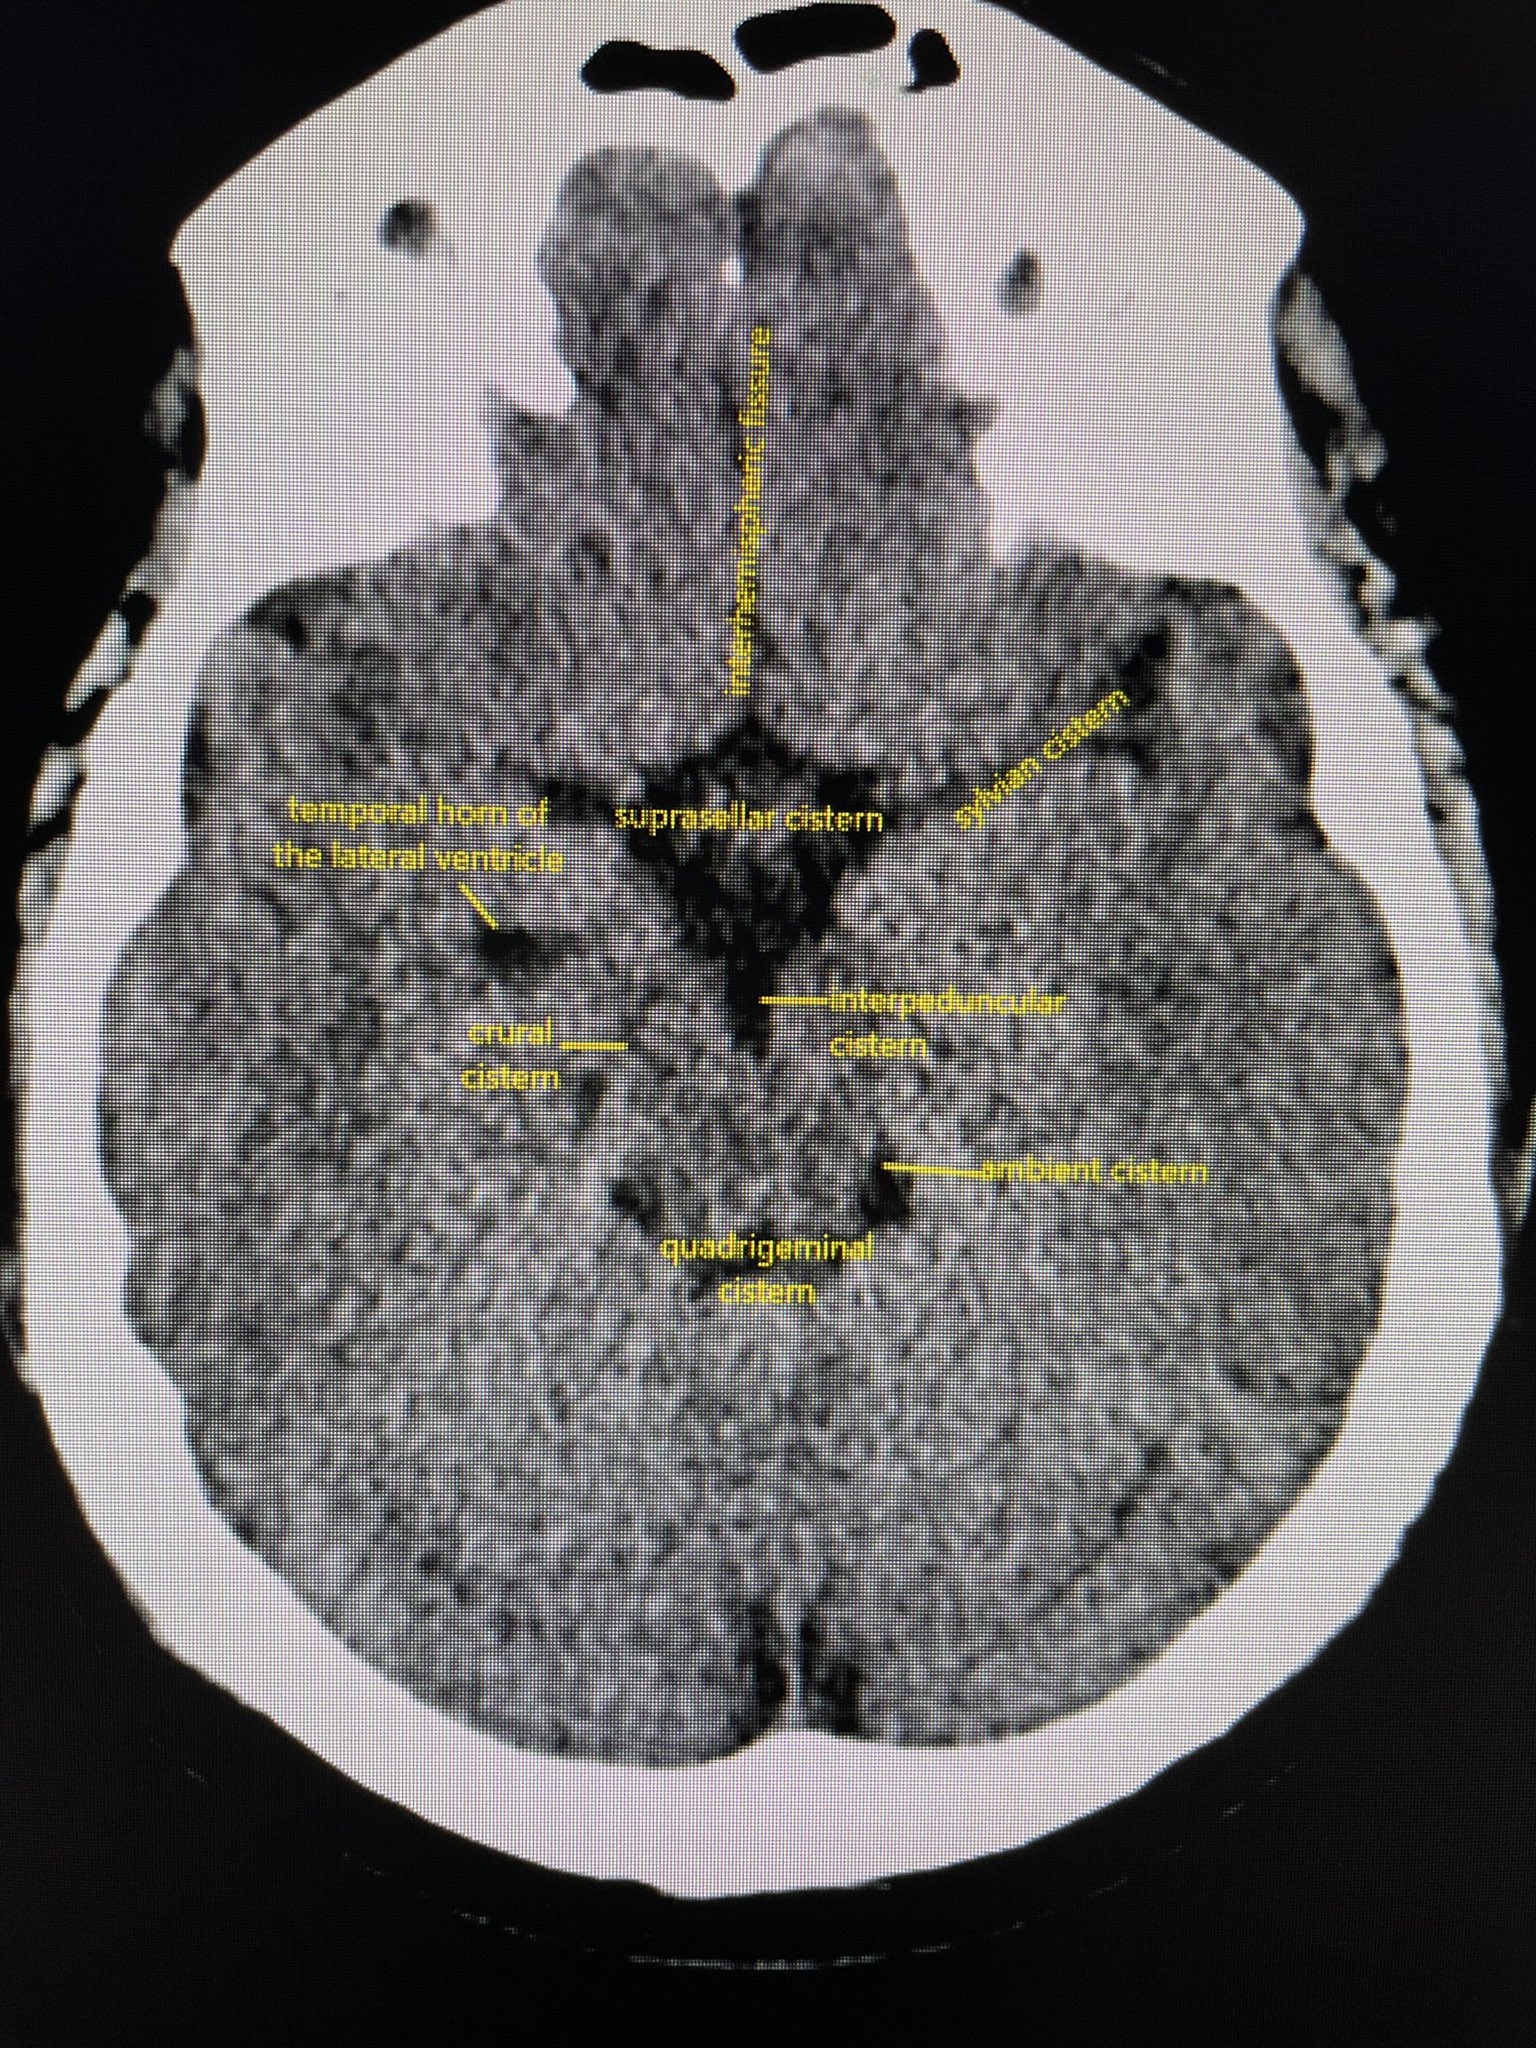

Clase 4 tac de cerebro y tec 2014 | PPT

Cerebral Cisterns - W-Radiology

Subarachnoid cisterns | Radiology Reference Article | Radiopaedia.org

4. Basal CSF cisterns | RANZCRPart1 Wiki | Fandom